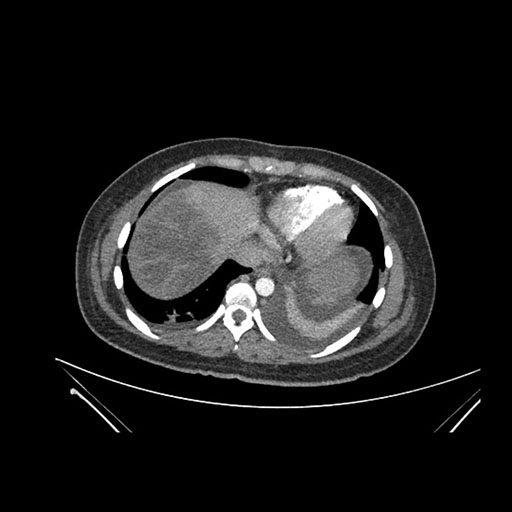

Imaging Analysis

Look through the patient's CT scan to identify any areas of concern for the necessary procedure.

Axial Arterial

Based on initial findings, which issue(s) would you be most concerned about?